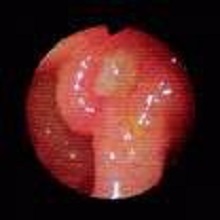

Општа болница Панчево може се, са изузетним поносом, похвалити да је набавила значајну медицинску опрему за одсек гастроентерологије са ендоскопском дијагностиком. Ова изузетно вредна набавка реализована је из средстава која су нашој болници додељена након спроведеног јавног конкурса Покрајинског секретаријата за здравство за доделу средстава за изградњу, одржавање и опремање здравствених установа чији је оснивач Аутономна покрајина Војводина. |